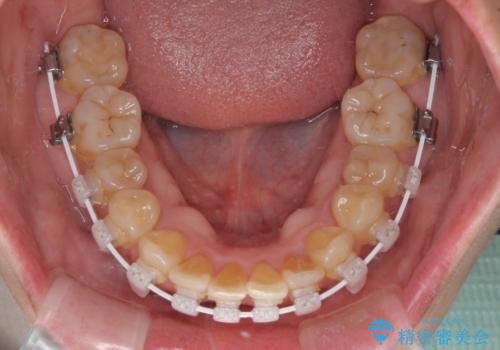

前歯のデコボコをワイヤー矯正できれいに整える

- 矯正装置

- 審美装置

- 前歯のデコボコと変色した前歯を気にして来院された患者様です。

抜歯矯正により口元を引っ込めることも検討しましたが、特に口元の突出感は気になっていないとのことで、非抜歯にてワイヤー装置で矯正治療を行うこととしました。

気になっていた前歯の変色も、矯正治療後にオールセラミッククラウンにて補綴治療を行うこととしました。

舌の突出癖により治療期間中に開咬となり、治療が長引きましたが、口元も治療前よりも引っ込めることができ、すっきりとした仕上がりとなりました。